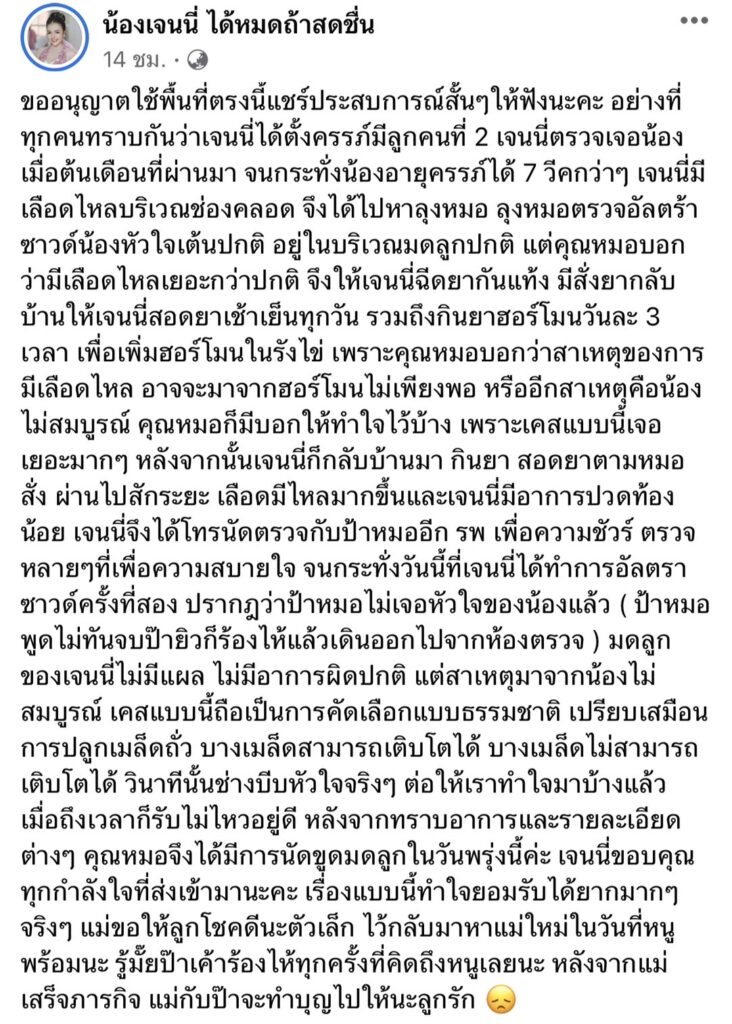

ทำเอาแฟนคลับแห่ส่งกำลังใจให้นักร้องสาว”เจนนี่ รัชนก หรือ เจนนี่ ได้หมดถ้าสดชื่น”ได้ออกมาแจ้งข่าวร้ายว่าตัวเองได้แท้งลูกคนที่2 เป็นที่เรียบร้อย และต่อมาเจ้าตัวก็ออกมาแชร์ประสบการณ์เรื่องนี้ โดยโพสต์ภาพพร้อมแคปชั่นว่า”

ขออนุญาตใช้พื้นที่ตรงนี้แชร์ประสบการณ์สั้นๆให้ฟังนะคะ อย่างที่ทุกคนทราบกันว่าเจนนี่ได้ตั้งครรภ์มีลูกคนที่ 2 เจนนี่ตรวจเจอน้องเมื่อต้นเดือนที่ผ่านมา จนกระทั่งน้องอายุครรภ์ได้ 7 วีคกว่าๆ เจนนี่มีเลือดไหลบริเวณช่องคลอด จึงได้ไปหาลุงหมอ ลุงหมอตรวจอัลตร้าซาวด์น้องหัวใจเต้นปกติ อยู่ในบริเวณมดลูกปกติ แต่คุณหมอบอกว่ามีเลือดไหลเยอะกว่าปกติ จึงให้เจนนี่ฉีดยากันแท้ง มีสั่งยากลับบ้านให้เจนนี่สอดยาเช้าเย็นทุกวัน รวมถึงกินยาฮอร์โมนวันละ 3 เวลา เพื่อเพิ่มฮอร์โมนในรังไข่ เพราะคุณหมอบอกว่าสาเหตุของการมีเลือดไหล อาจจะมาจากฮอร์โมนไม่เพียงพอ หรืออีกสาเหตุคือน้องไม่สมบูรณ์ คุณหมอก็มีบอกให้ทำใจไว้บ้าง เพราะเคสแบบนี้เจอเยอะมากๆ หลังจากนั้นเจนนี่ก็กลับบ้านมา กินยา สอดยาตามหมอสั่ง ผ่านไปสักระยะ เลือดมีไหลมากขึ้นและเจนนี่มีอาการปวดท้องน้อย เจนนี่จึงได้โทรนัดตรวจกับป้าหมออีก รพ เพื่อความชัวร์ ตรวจหลายๆที่เพื่อความสบายใจ จนกระทั่งวันนี้ที่เจนนี่ได้ทำการอัลตราซาวด์ครั้งที่สอง ปรากฎว่าป้าหมอไม่เจอหัวใจของน้องแล้ว ( ป้าหมอพูดไม่ทันจบป๊ายิวก็ร้องไห้แล้วเดินออกไปจากห้องตรวจ ) มดลูกของเจนนี่ไม่มีแผล ไม่มีอาการผิดปกติ แต่สาเหตุมาจากน้องไม่สมบูรณ์ เคสแบบนี้ถือเป็นการคัดเลือกแบบธรรมชาติ เปรียบเสมือนการปลูกเมล็ดถั่ว บางเมล็ดสามารถเติบโตได้ บางเมล็ดไม่สามารถเติบโตได้ วินาทีนั้นช่างบีบหัวใจจริงๆ ต่อให้เราทำใจมาบ้างแล้ว เมื่อถึงเวลาก็รับไม่ไหวอยู่ดี หลังจากทราบอาการและรายละเอียดต่างๆ คุณหมอจึงได้มีการนัดขูดมดลูกในวันพรุ่งนี้ค่ะ เจนนี่ขอบคุณทุกกำลังใจที่ส่งเข้ามานะคะ เรื่องแบบนี้ทำใจยอมรับได้ยากมากๆจริงๆ แม่ขอให้ลูกโชคดีนะตัวเล็ก ไว้กลับมาหาแม่ใหม่ในวันที่หนูพร้อมนะ รู้มั๊ยป๊าเค้าร้องไห้ทุกครั้งที่คิดถึงหนูเลยนะ หลังจากแม่เสร็จภารกิจ แม่กับป๊าจะทำบุญไปให้นะลูกรัก 😞

และล่าสุดทางด้านสาว”เจนนี่”ได้ออกมาปล่อยคลิป สามี”ยิว ฉัตรมงคล”นอนกอดน้อง”ยูจิน” พร้อมกับหลั่งน้ำตาเสียใจกับเหตุการณ์ที่เกิดขึ้น ซึ่งในคลิปยังได้พูดว่า ลูกเป็นยังไงบ้างก็ไม่รู้เลย และไม่รู้ว่าลูกเป็นผู้หญิงหรือผู้ชายซี่งมีสาวเจนนี่คอยปลอบอยู่ข้างๆ